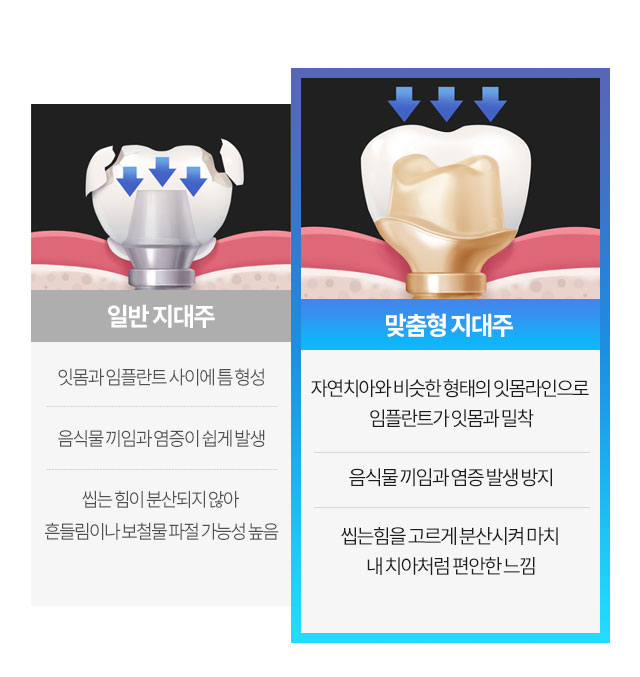

빈틈없는 수술, 빈틈없는 잇몸

고르다치과는 맞춤형

임플란트를 사용합니다.

환자의 10년 후 치아까지 생각하는 신중한 치료